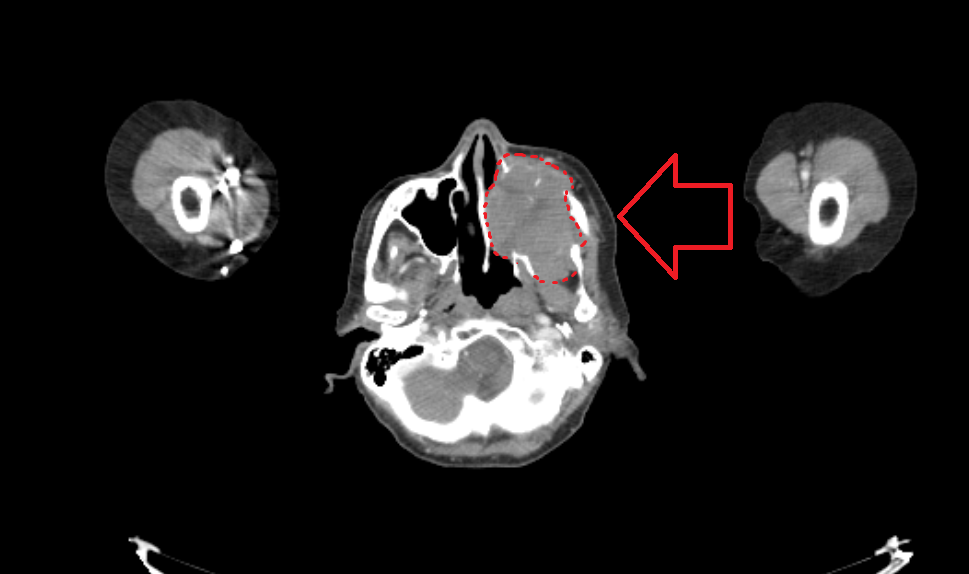

Стрелка указывает на опухоль, обведенную крастным пунктиром. На снимке хорошо видно, насколько левая половина лица больше правой

Менее чем через 2 месяца после появления самых первых симптомов, опухоль достигала размеров 46х47х53мм, и метастазировала в шейные лимфоузлы слева.